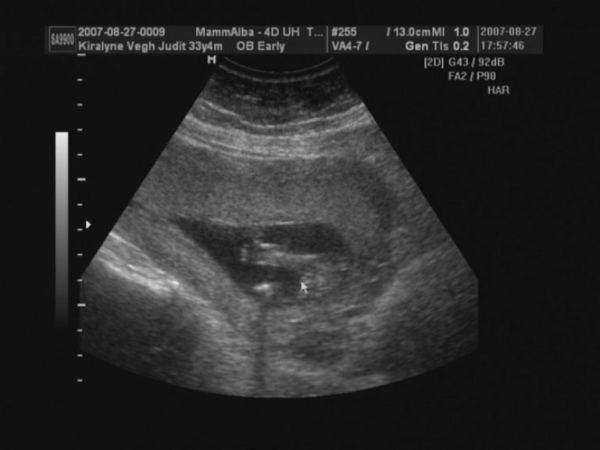

Judy, nagyon szép babátok van, gyerekek mit szóltak???